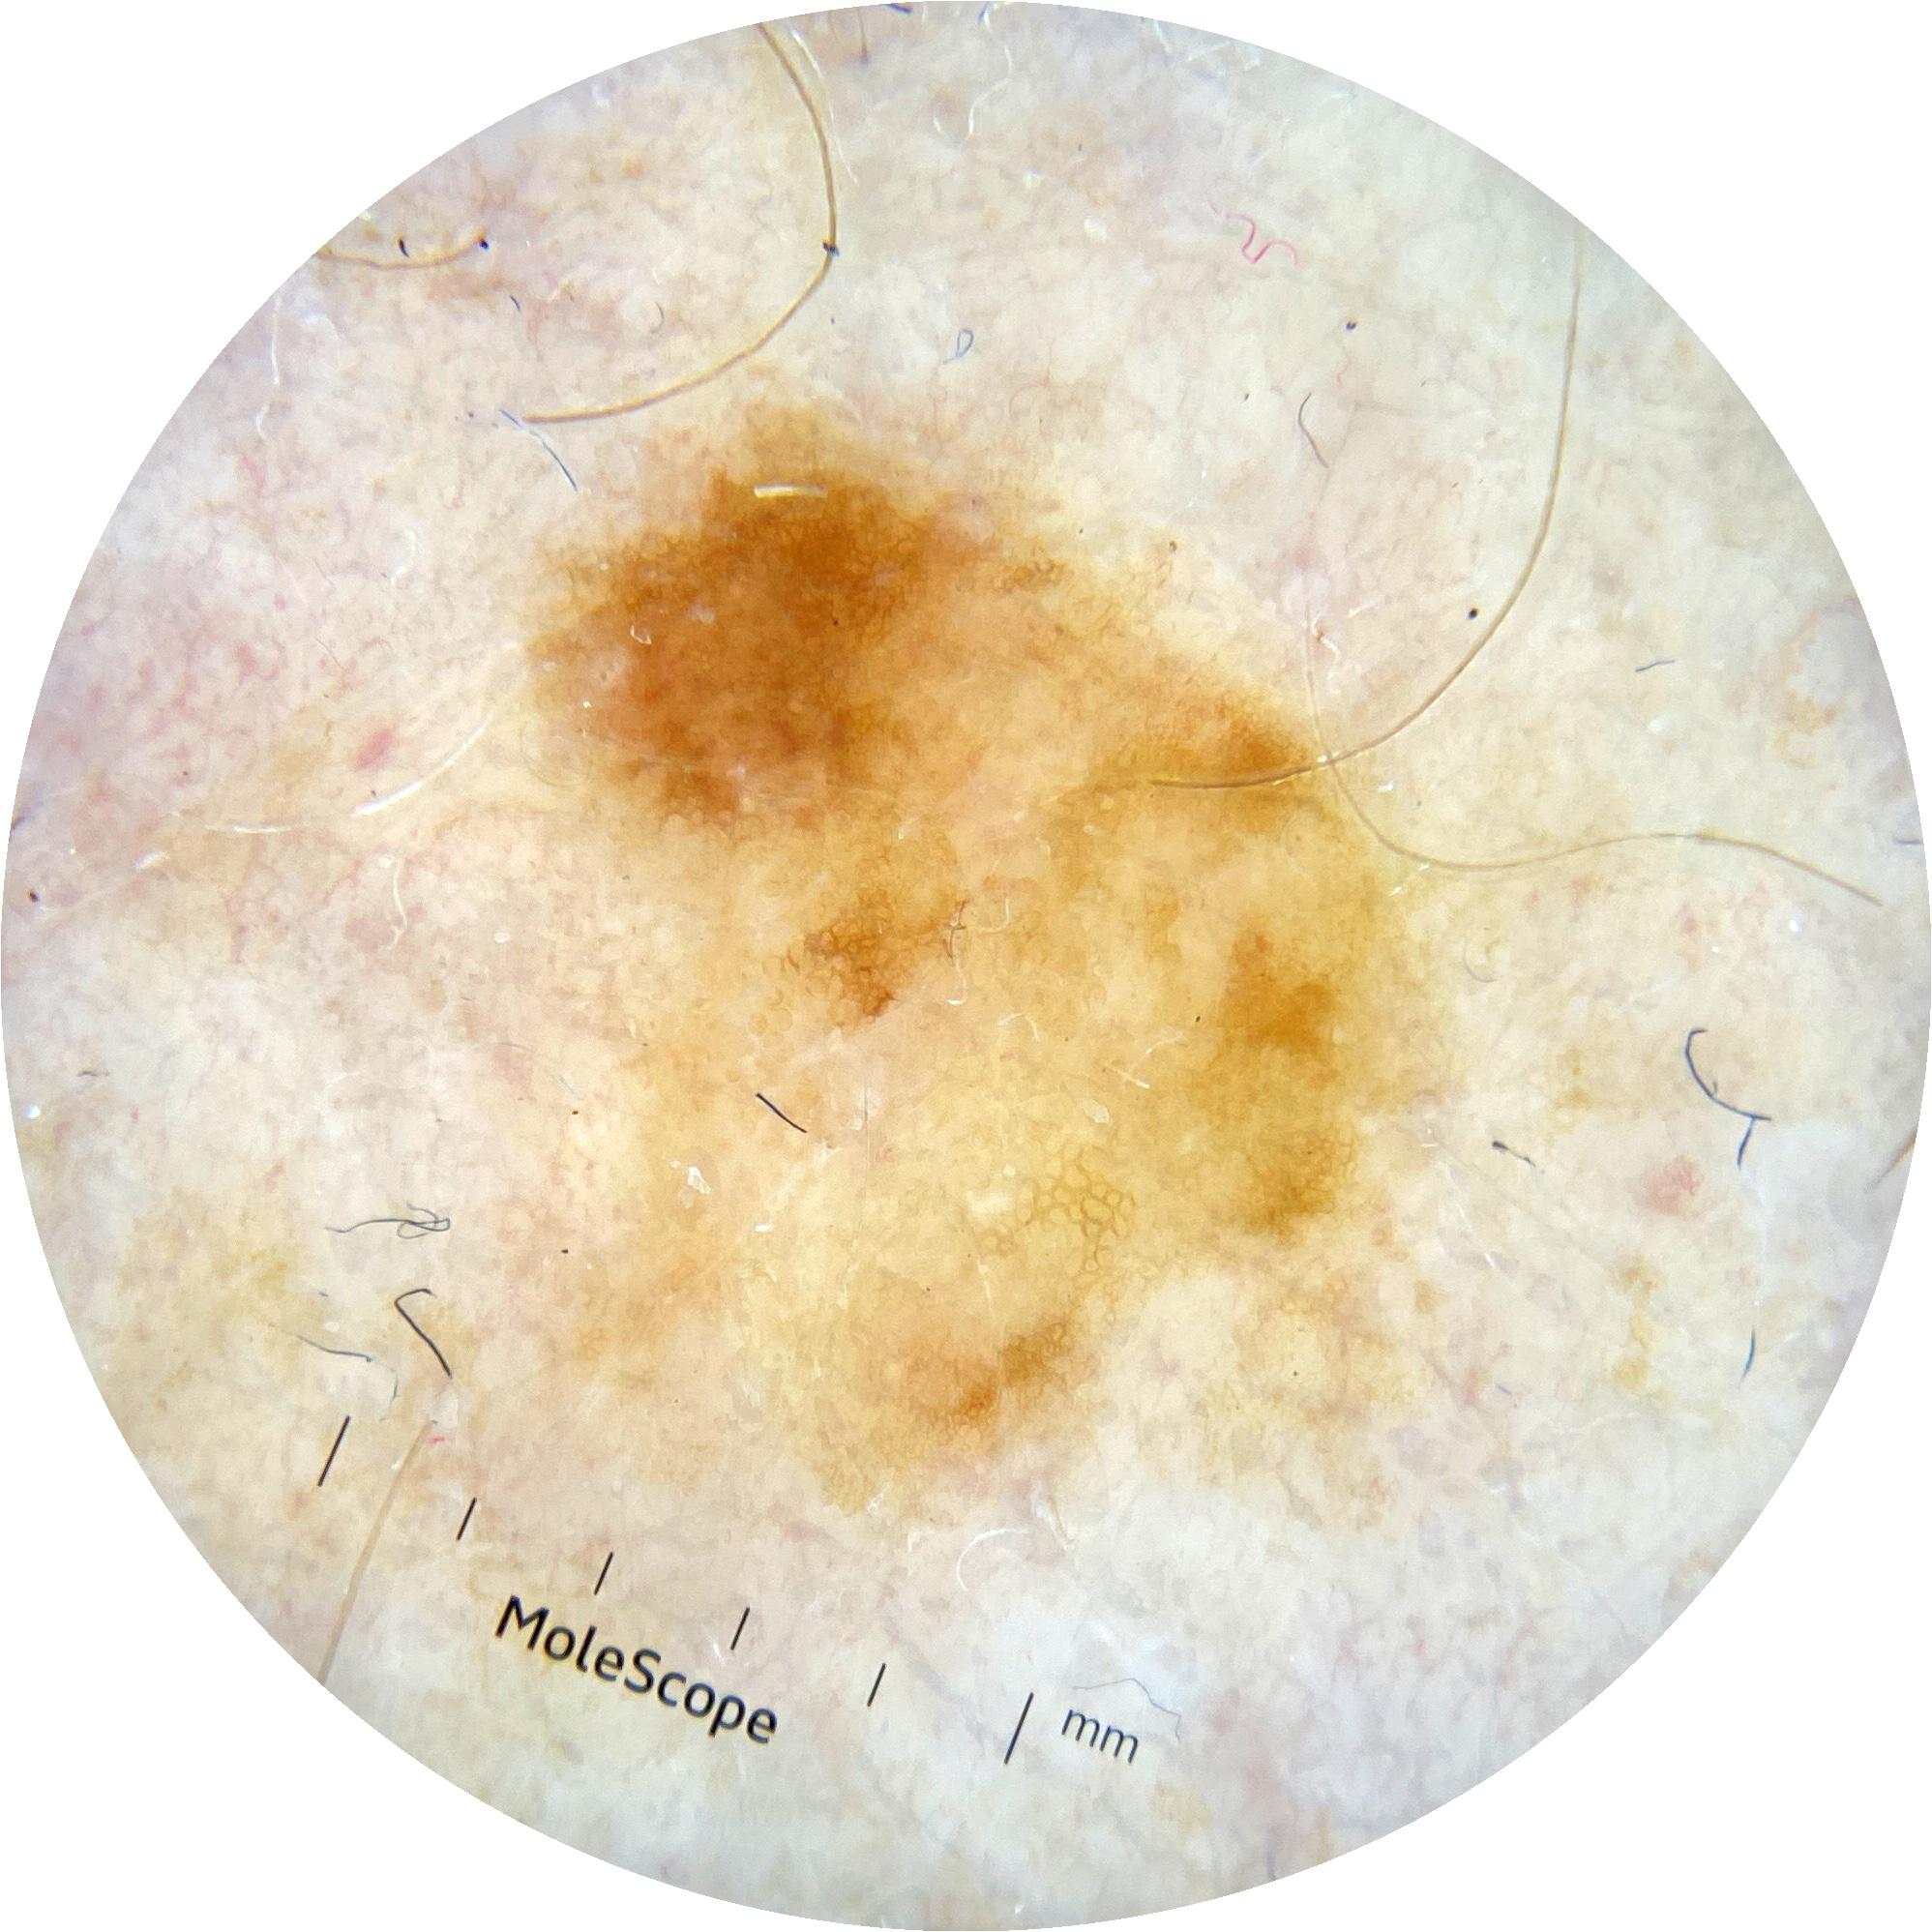

ISIC_7952191

Information

2029 x 2029

MEL-SELF Trial, https://www.sydney.edu.au/medicine-health/our-research/research-centres/melself-project.html

Field Value

acquisition_day 297

age_approx 70

anatom_site_1 Upper extremity

anatom_site_general upper extremity

concomitant_biopsy False

diagnosis_1 Benign

diagnosis_confirm_type single image expert consensus

family_hx_mm False

image_manipulation instrument only

image_type dermoscopic

lesion_id IL_5276311

patient_id IP_4227222

personal_hx_mm True

sex female